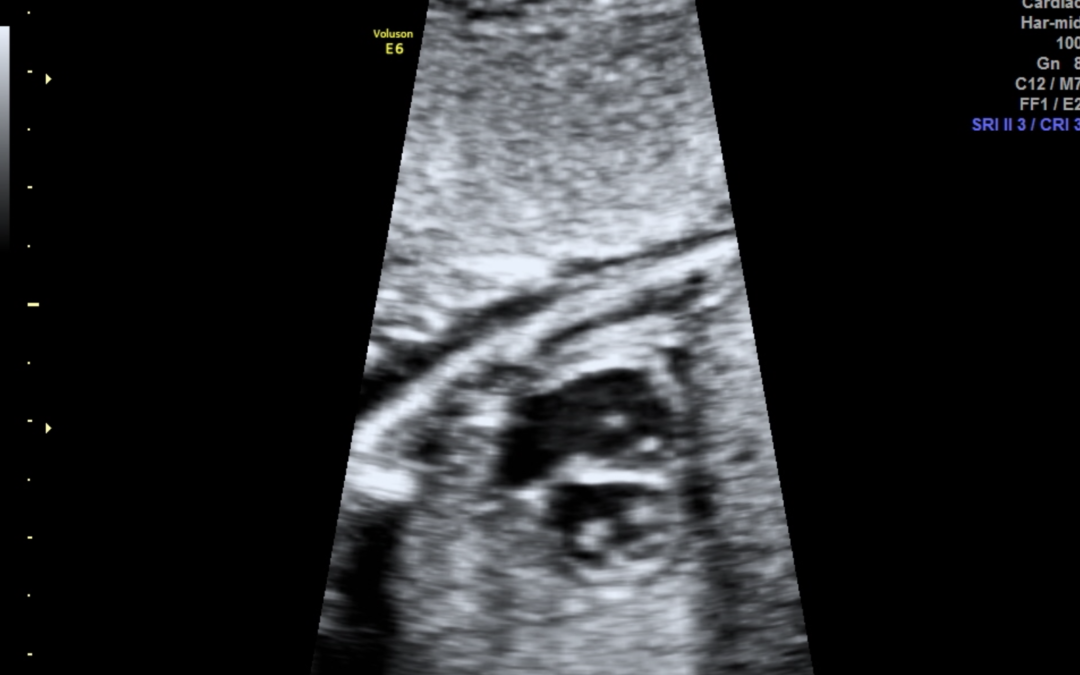

Ο έλεγχος της εμβρυϊκής καρδιάς στο δεύτερο τρίμηνο είναι πια πλήρης δηλαδή ελέγχεται τόσο η ανατομία όσο και η λειτουργία και η ανάπτυξη της εμβρυϊκής καρδιάς. Είναι εφικτό να διαγνωσθούν σχεδόν όλες οι μείζονες και οι ελάσσονες συγγενείς καρδιοπάθειες. Κατά τον προγεννητικό έλεγχο δεν δύναται να διαγνωσθούν κάποιες μυοκαρδιοπάθειες, οι καναλοπάθειες, οι ανωμαλίες των στεφανιαίων αγγείων, το μεσοκολπικό έλλειμμα, η παραμονή του βοταλλείου πόρου, οι υποβαλβιδικές στενώσεις και η μερική ανώμαλη επαναφορά των πνευμονικών φλεβών.

Η εξέταση πρέπει να γίνεται από παιδοκαρδιολόγο εξειδικευμένο στην εμβρυϊκή καρδιολογία.